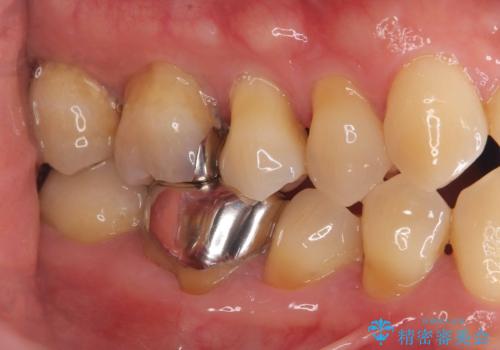

- 「銀歯を白くしたい」を主訴に来院された患者様です。銀歯を外し虫歯を除去後、オールセラミッククラウンで治療を行いました。

銀歯を外して内部の虫歯を丁寧に除去した後、オールセラミッククラウンにて修復を行いました。審美性と機能性の両面で改善が得られ、患者様にもご満足いただきました。